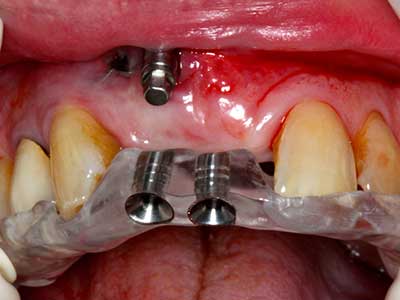

Bone tissue is not simply a mineral structure but also contains a substantial proportion of collagen fibres. This means it not only has good compressive strength but also a degree of flexibility, which can be taken advantage of when performing bone augmentations. In the classical expansion procedure using bone splitting, the atrophied alveolar ridge is split longitudinally and carefully expanded after reaching an adequate osteotomy depth (Fig. 13-16), ideally without substantial removal of the periosteum (Brugnami, Caiazzo et al. 2014, Stricker, Fleiner et al. 2014). Screw and plate systems with increasing expansion distance have proven effective in separating the two bone lamellae while remaining below the fracture threshold. In general, residual bone widths of at least 3–4 mm are required (Chiapasco, Zaniboni et al. 2006) to guarantee adequate flexibility and sufficient bone coverage of the future implants. If necessary, a vertical relief osteotomy on one or both sides can improve flexibility. A combination with additional augmentation techniques, particularly on the buccal side, has been described as an alternative to the classical technique.

The splitting procedure is particularly atraumatic and there is no significant loss of dimension when using piezosaws, and there are no significant differences between implants in split jaws and implants in an alveolar ridge without a bone deficit (Chiapasco, Zaniboni et al. 2006, Danza, Guidi et al. 2009). However, sufficient continuous irrigation is essential, particularly with locally restricted and deep splitting to prevent thermal stress in the apical osteotomy regions.

Fig. 13: Adequate irrigation with the 4-mm residual bone width is essential for this 52-year-old patient during the bone splitting.

Fig. 14: Placement of four tapered RSX implants (Bego Implant Systems, Bremen).

Fig. 15: The one-year follow-up x-ray examination shows stable conditions at the bone level.

Fig. 16: The intraoral conditions are also stable with embedding of the implants in keratinized gingiva.